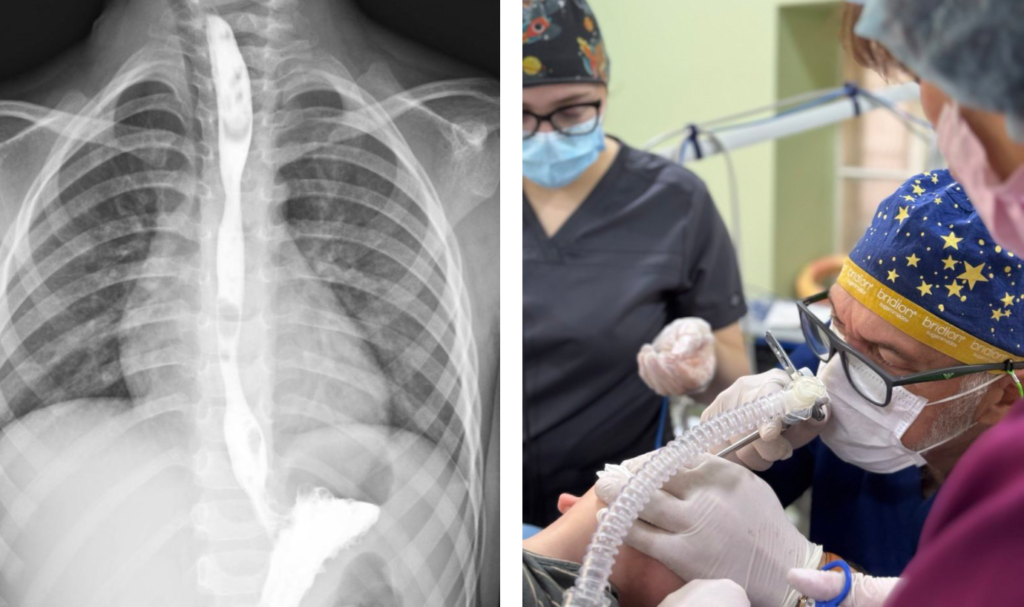

Два роки боротьби за можливість просто їсти. У 3 роки хлопчик випадково випив засіб для чищення кухні — і отримав тяжкий опік стравоходу. Лікарям довелося пройти довгий і складний шлях, аби повернути дитині нормальне життя.

Команда торакальних хірургів Центру дитячої медицини врятувала 3-річну дитину, яка випадково проковтнула засіб для очищення побутової техніки від жиру.

Хімічна речовина спричинила тяжкий опік стравоходу. На момент госпіталізації стан малюка був вкрай важким: він не міг самостійно приймати їжу, страждав від сильного болю, слинотечі та блювання. Дитину негайно доправили до відділення інтенсивної терапії.

Через неможливість ентерального харчування та значне ураження стравоходу лікарі виконали оперативне втручання — накладання гастростоми. Це дозволило забезпечити повноцінне харчування без навантаження на ушкоджений орган і стабілізувати стан дитини.

Згодом у хлопчика сформувався критичний стеноз стравоходу — суттєве звуження просвіту, яке повністю унеможливлювало прийом їжі через рот.

Після консультацій мультидисциплінарної команди медики ухвалили рішення провести серію балонних дилатацій — малоінвазивних ендоскопічних процедур, під час яких звужену ділянку поступово розширюють спеціальним балоном без хірургічних розрізів.

“Це була складна, тривала та поетапна робота, але завдяки злагодженим діям команди нам вдалося уникнути великої травматичної операції”, — зазначив керівник Клініки торакальної хірургії та реконструктивної урології у дітей лікарні “Охматдит” Олег Ленів.

До лікування долучилися торакальні хірурги, анестезіологи, медсестри, фахівці інтенсивної терапії та рентгенолог Зеновія Жидяк. Зокрема, у команді працювали торакальний хірург Роман Ковальський та анестезіолог Віра Приймакова разом із колегами відділення.